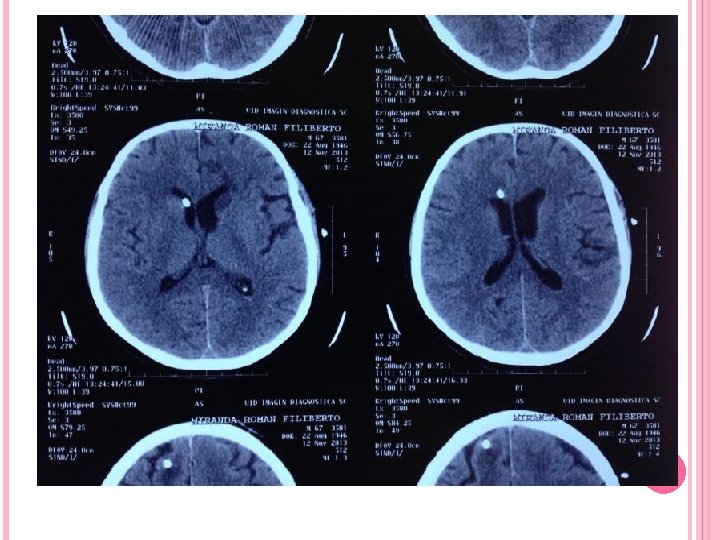

ANGIOGRAFÍA CEREBRAL Antes era fundamental el estudio del síndrome hidrocefálico, actualmente han quedado relegadas. Solo se utilizan para estudio de malformaciones vasculares que pudieran desencadenar hidrocefalia TOMOGRAFÍA CEREBRAL MÉTODO DE ELECCIÓN Tamaño de Cavidades ventriculares Causa Etiológica Villarejo Francisco. Martínez Lage Juan F. “NEUROCIRUGÍA PEDIÁTRICA”. Ediciones Ergón. Madrid España 2001 Neumoencefalografía Ventriculografía Cisternografía isotópica

Criterios para TAC Presencia de dilatación ventricular Hipodensidad en polos occipitales y frontales periventriculares Borramiento de los surcos cerebrales INDICE DE EVANS : igual o superior a 0. 30 debe considerarse patológico Cuernos temporales con diámetro mayor a 2 mm Lopez Ojeda Pablo, DIAGNOSTICO Y TRATAMIENTO DE LA HIDROCEFALIA CRONICA EN EL ADULTO, Barcelona hospital universitario 2009

Criterios para TAC FH/ID >0. 5 Abombamiento de los cuernos frontales y ventrículos laterales

Lopez Ojeda Pablo, DIAGNOSTICO Y TRATAMIENTO DE LA HIDROCEFALIA CRONICA EN EL ADULTO, Barcelona hospital universitario 2009